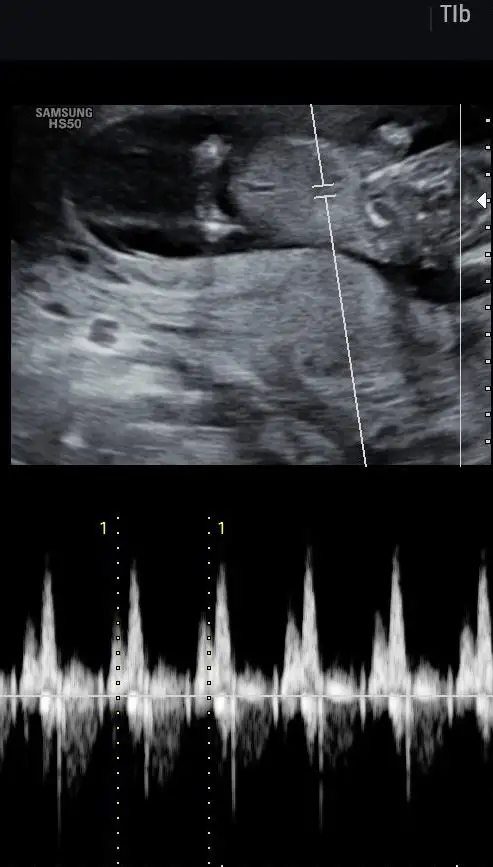

Kızlar merhaba, banada 11 artı 5 te yüzde 80 kız dedi, ama netten bakıyorum daha dıyo üreme organı olusma aşamasında.. Aslında bana farketmez ama insan merak ediyor neden bu kadar erken soyledi ki şüphede kaldık.

Doktorların yanılma payı her zaman var ama daha cinsiyet tomurcukları yeni oluşuyor. 16 17 haftadan önce söylenenlerin tutmama durumu daha yüksek

Ben de 11+6’da oglum olacagini ogrenmistim, oglum oldu. Bakan doktor cok iyi bi doktordu. Yani doktoruna gore degise debilir degismeye debilir